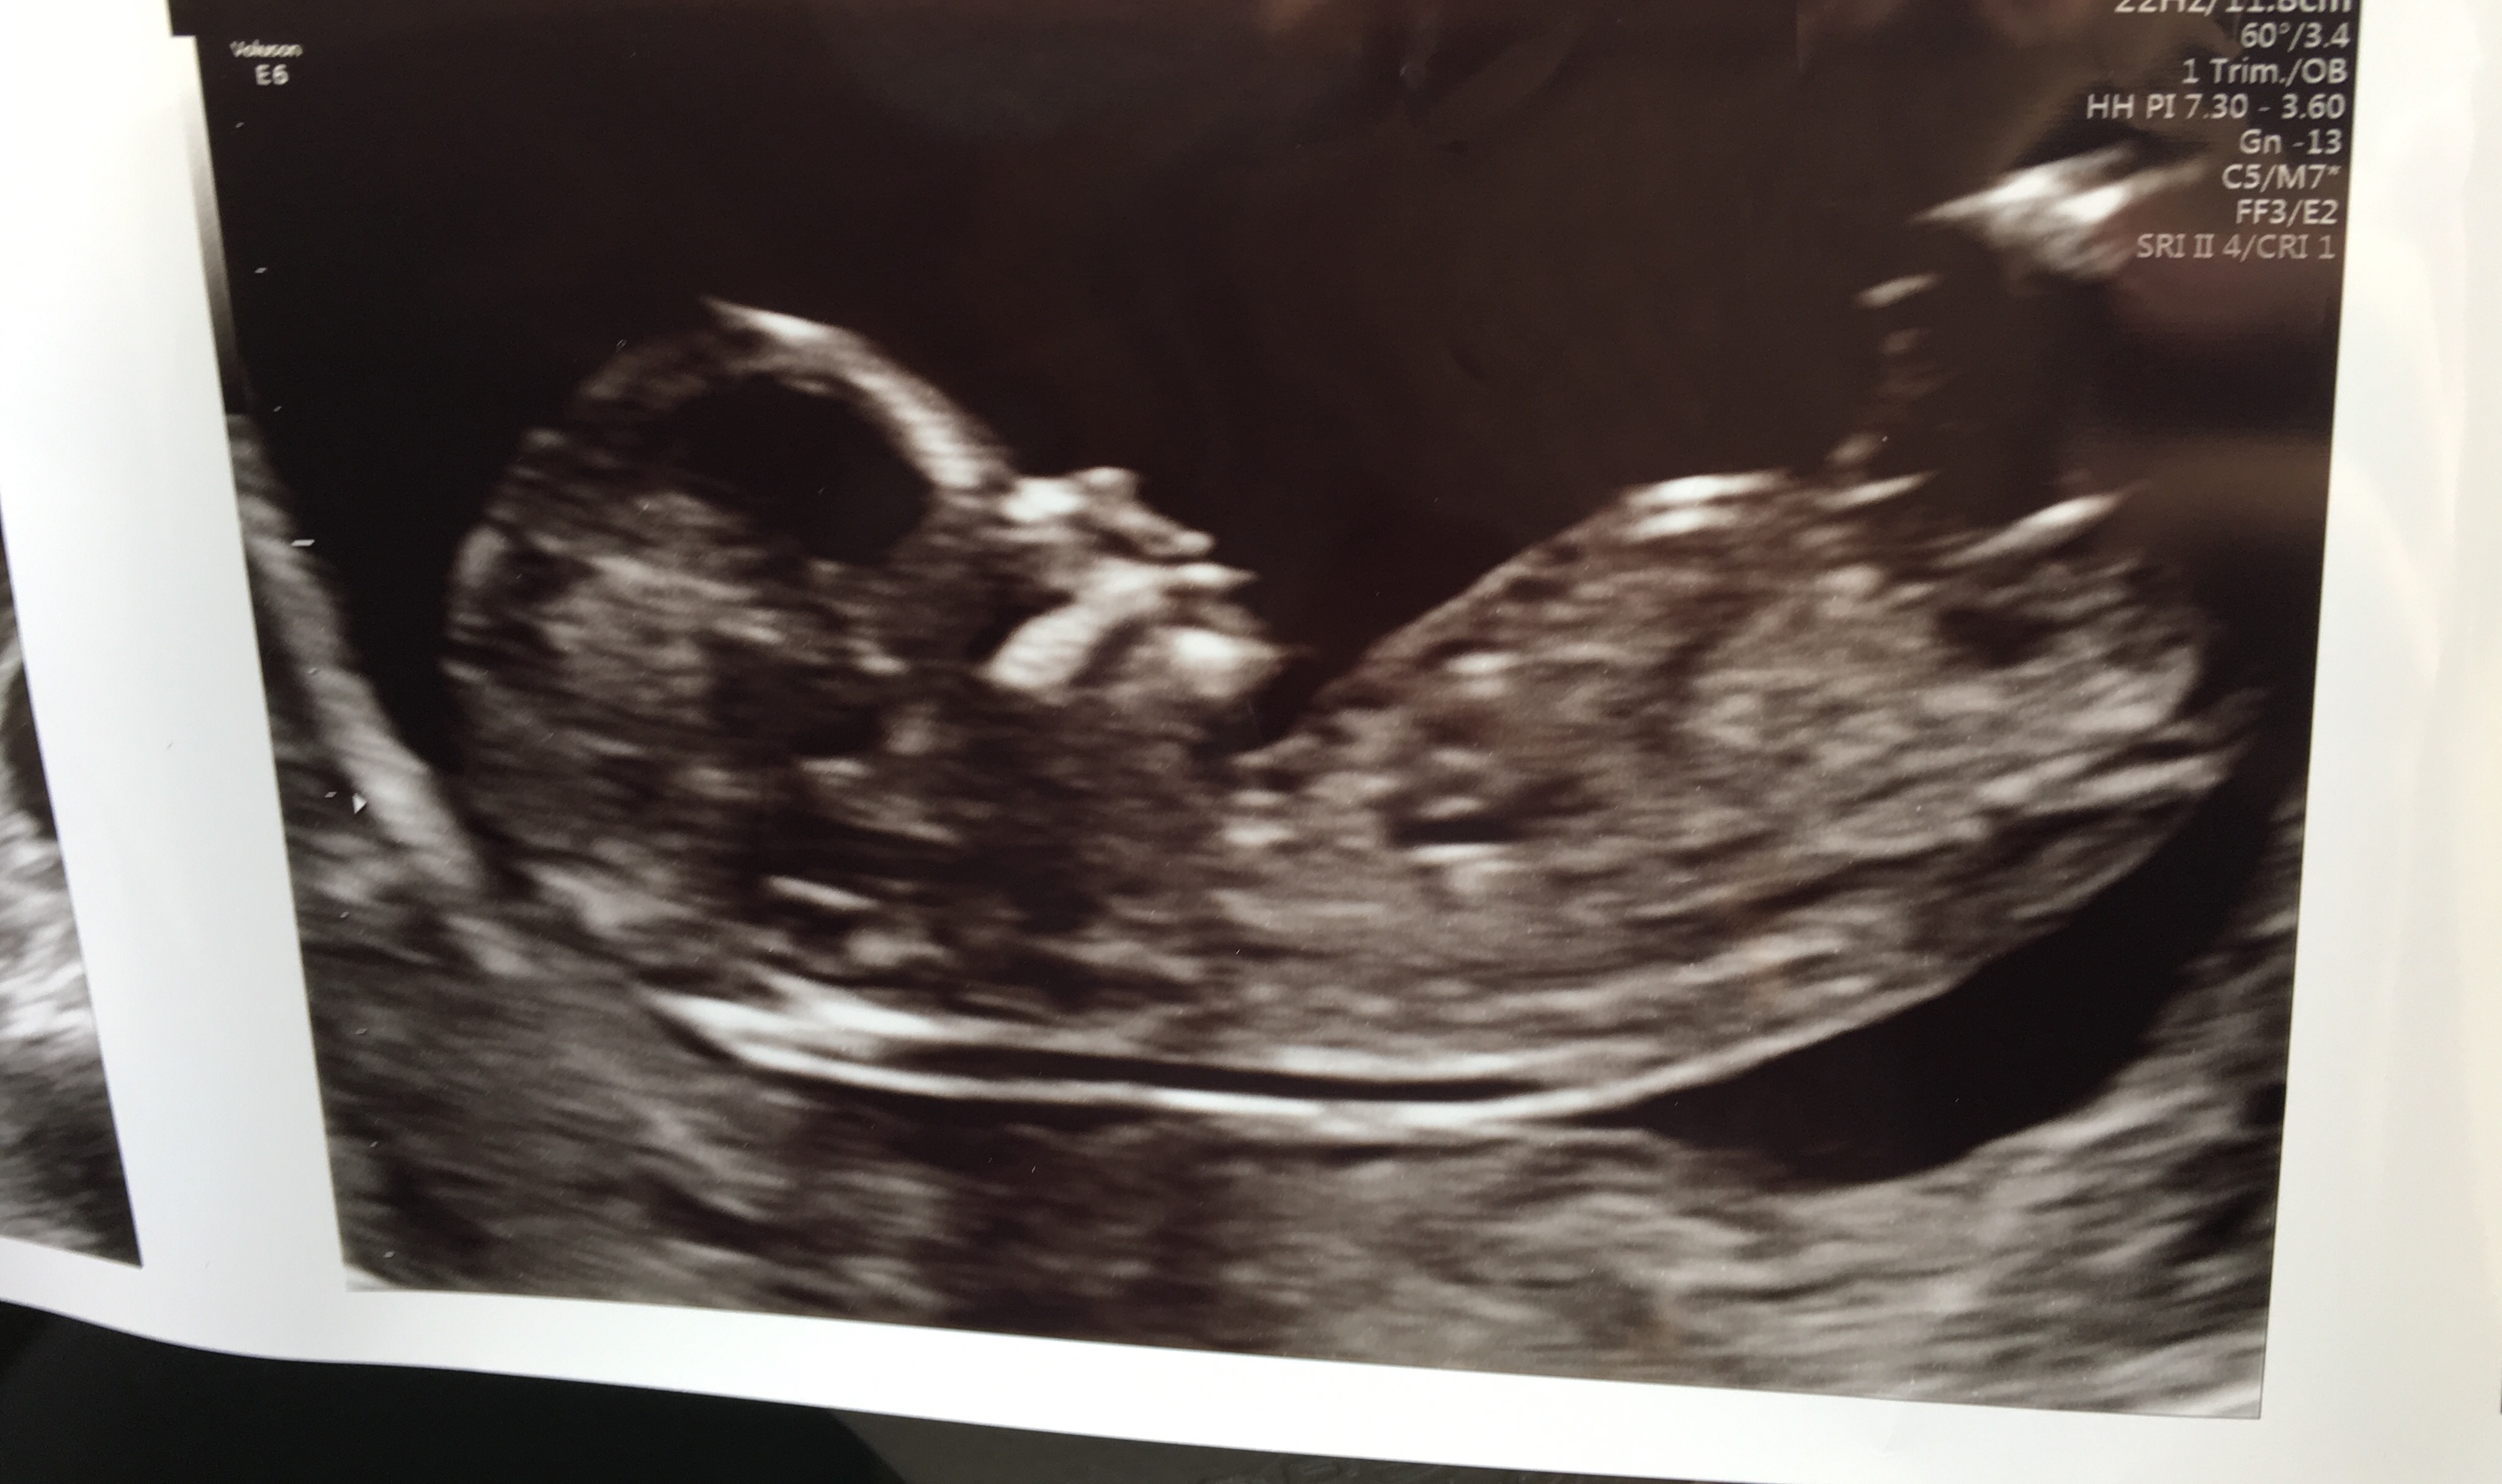

We are team green but I still would love nub guesses! We had our NIPT ultrasound today and I’m definitely curious what everyone else sees based on this. What do you think?![]()

Thread: 12w 6d Nub - Boy or Girl?

12w 6d Nub - Boy or Girl?

Leaning slightly girl but the nub looks a bit cut off so hard to say.

That is a really tricky one! In one picture I would have said girly

But on another one I can see some stacking on the nub so would indicate a boy

Looks like it's 50/50 still!!

tentative pink lean but earlier and less clear than I'd like

Just wanted to let everyone know that it’s a boy! Our sway failed by we’re so in love with our little guy who arrived 2 weeks early on May 31st!